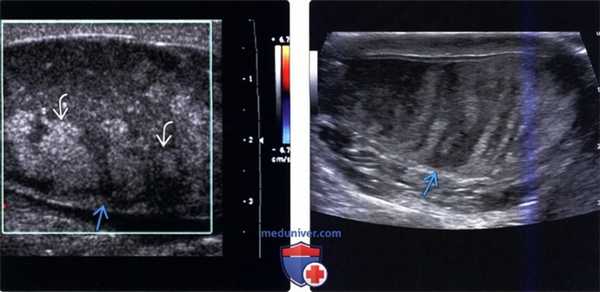

(Слева) Цветовое допплеровское картирование, сагиттальная плоскость, левое яичко: визуализируется увеличенное гетерогенное аваскулярное яичко с множеством гиперэхогенных участков 1В. Патоморфологическое исследование подтвердило геморрагический инфаркт и перекрут >360°.

(Справа) В-режим, сагиттальная плоскость, левое яичко: определяется увеличенное гетерогенное яичко полосатого вида, что говорит о частичных инфарктах. У пациента в анамнезе частичный перекрут яичка.